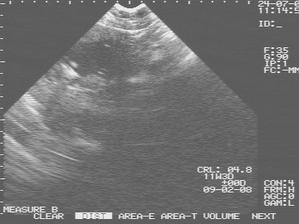

28.8.2007 AMC -----